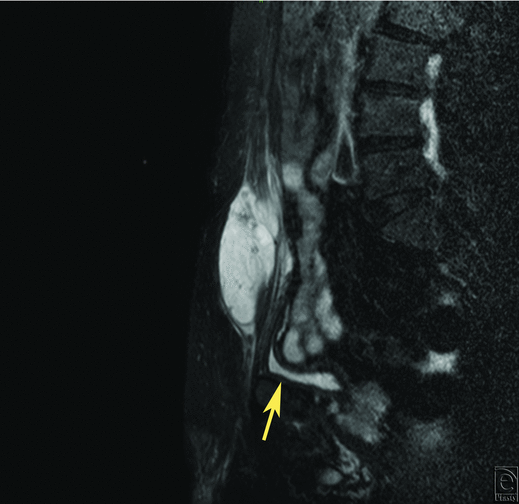

A 75-year-old man experienced an induration with pain on his lower abdominal wall. Since the tumor increased gradually, he consulted a plastic surgeon. Magnetic resonance imaging revealed a tumor in his right rectus abdominis muscle. Magnetic resonance imaging showed a heterogeneously contrast-enhancing mass involving his right rectus abdominis muscle (Fig 1). The patient underwent a biopsy at the Department of Orthopaedic Surgery in our hospital. Low-grade MFS was diagnosed histopathologically and the patient was referred to our department for further management including reconstructive surgery. No other lesions were detected on whole-body fluorodeoxyglucose-positron emission tomography (PET) scanning. At this point, there was no apparent evidence whether the tumor invaded into the abdominal cavity or not.

| Figure 2. Intraoperative view. (a). Skin incision line. (b). The tumor invading the abdominal cavity (arrow). |